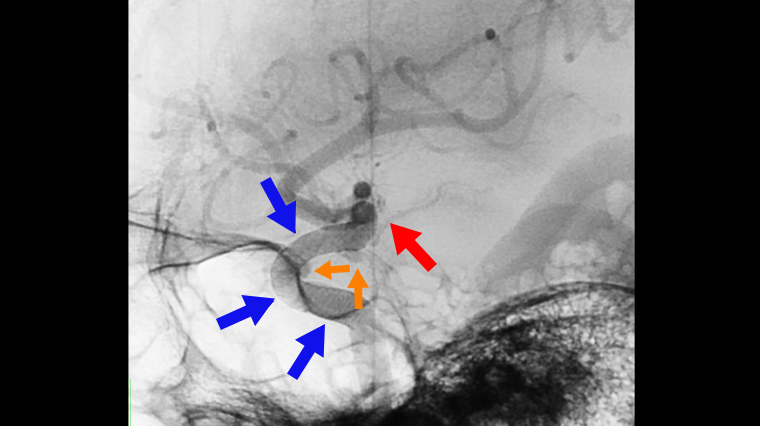

▲醫師小心避開前脈絡叢動脈(紅箭頭標示處),以血流導向裝置(藍箭頭標示處),治療患者的2顆腦動脈瘤(橘箭頭標示)。(圖/衛生福利部台北醫院提供)

針對患者的情況,胡成全坦言,由於病人的2顆動脈瘤長在顱內內頸動脈垂體遠端,血流衝擊2顆腦動脈瘤,此處動脈瘤若破裂,以外科手術夾除也相當不易,幸好及早發現,因此立即採取過血流導向裝置置放手術,精準放置後,血流流向已恢復正常,原先腦動脈瘤的不正常血流顯著減少,已解除致命危機。

關於血流導向裝置置放手術,胡成全說,這是屬於較新式的腦部微創手術,又被稱為動脈瘤栓塞手術。過程中利用質地軟、緻密的軟金屬線編織的密網支架,放入血管腔內導流血液,避免血液流入動脈瘤囊內造成出血,在放置支架時,也必須小心避開如前脈絡叢動脈…等位置,否則可能造成肢體偏癱、肢體感覺受損、視力受損等狀況。